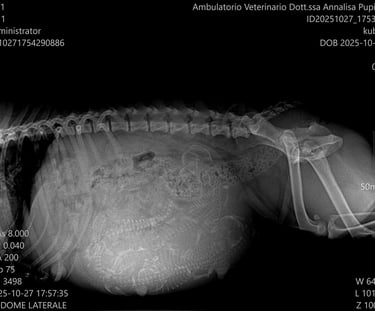

Tra il 55° e il 57° giorno di gravidanza, accompagniamo nuovamente la futura mamma in clinica per effettuare un’ecografia di controllo e una radiografia addominale.

L’ecografia ci permette di monitorare il benessere dei cuccioli, osservando il battito cardiaco e le condizioni generali all’interno dell’utero.

La radiografia, invece, ci fornisce un’informazione fondamentale: il numero esatto dei cuccioli in arrivo. Questo dato è molto utile per prepararsi al parto e seguire con attenzione ogni fase della nascita.